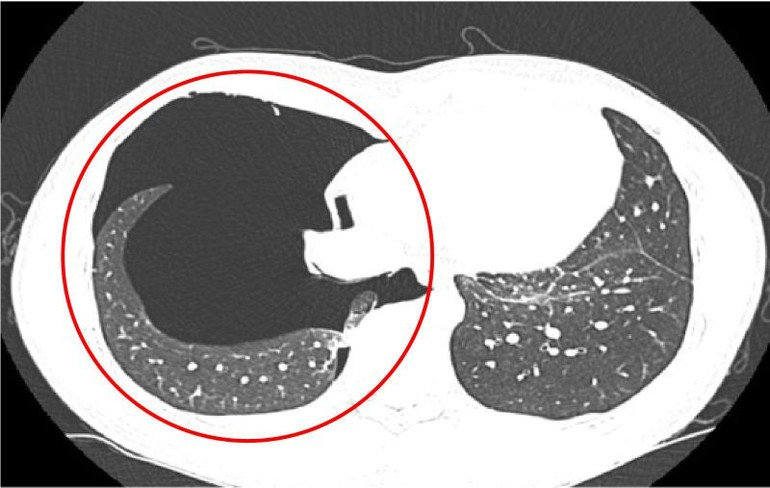

Tại bệnh viện, các bác sĩ tiếp tục chỉ định anh A. chụp cắt lớp vi tính lồng ngực nhằm đánh giá chính xác mức độ tổn thương. Kết quả xác nhận bệnh nhân bị tràn khí khoang màng phổi phải mức độ vừa đến nhiều, kèm theo tổn thương nhu mô phổi (đám đông đặc ở thùy trên và phân thùy S5 phổi phải). Tình trạng này được nhận định do chấn thương phổi trong lúc gắng sức.

Hình ảnh chụp cắt lớp vi tính cho thấy tràn khí khoang màng phổi phải mức độ vừa đến nhiều.